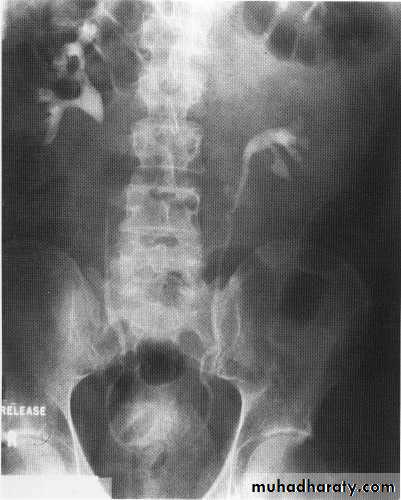

Pelviureteric junction obstruction

This condition has a spectrumof severity from severe antenatal hydronephrosis with global cortical loss to radiologically demonstrable hydronephrosis in theadult without apparent symptoms or loss of renal functionUp to 20%are associated with an accessory renal artery running across thePUJ, which may be visible on the IVU as a smooth indentation.

During the acute episode there are features on IVU of severe acute obstruction, which include a delayed, increasingly dense nephrogram and delayed appearance (sometimes up to 24 h or more) of contrast within the collecting system. When opacification occurs it demonstrates clubbed calyces and a dilated pelvis